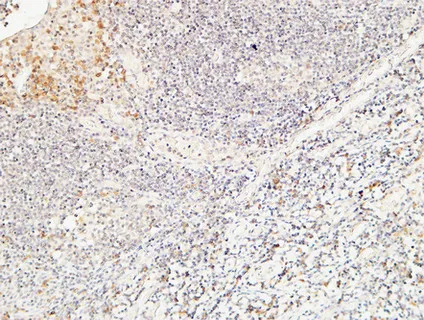

CD244 Rabbit Polyclonal Antibody

Cat: APRab08306

Size1:50μl Price1:$118

Size2:100μl Price2:$220

Size3:500μl Price3:$980

Size2:100μl Price2:$220

Size3:500μl Price3:$980